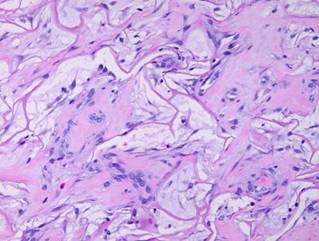

Figure 2

This micrograph, 17 days after placement, shows the sizes and relationships of cells and matrix.  The smallest dark round lymphoid cells are the pioneer cells, the larger flatter ones are the transitional cells.